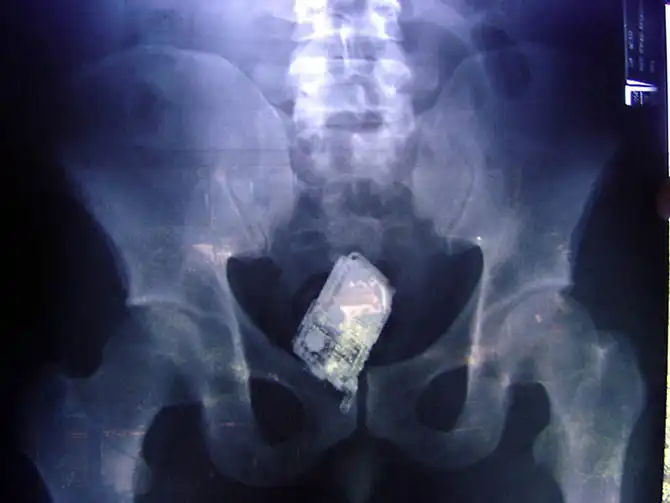

Мобильник в кишечнике заключенного.